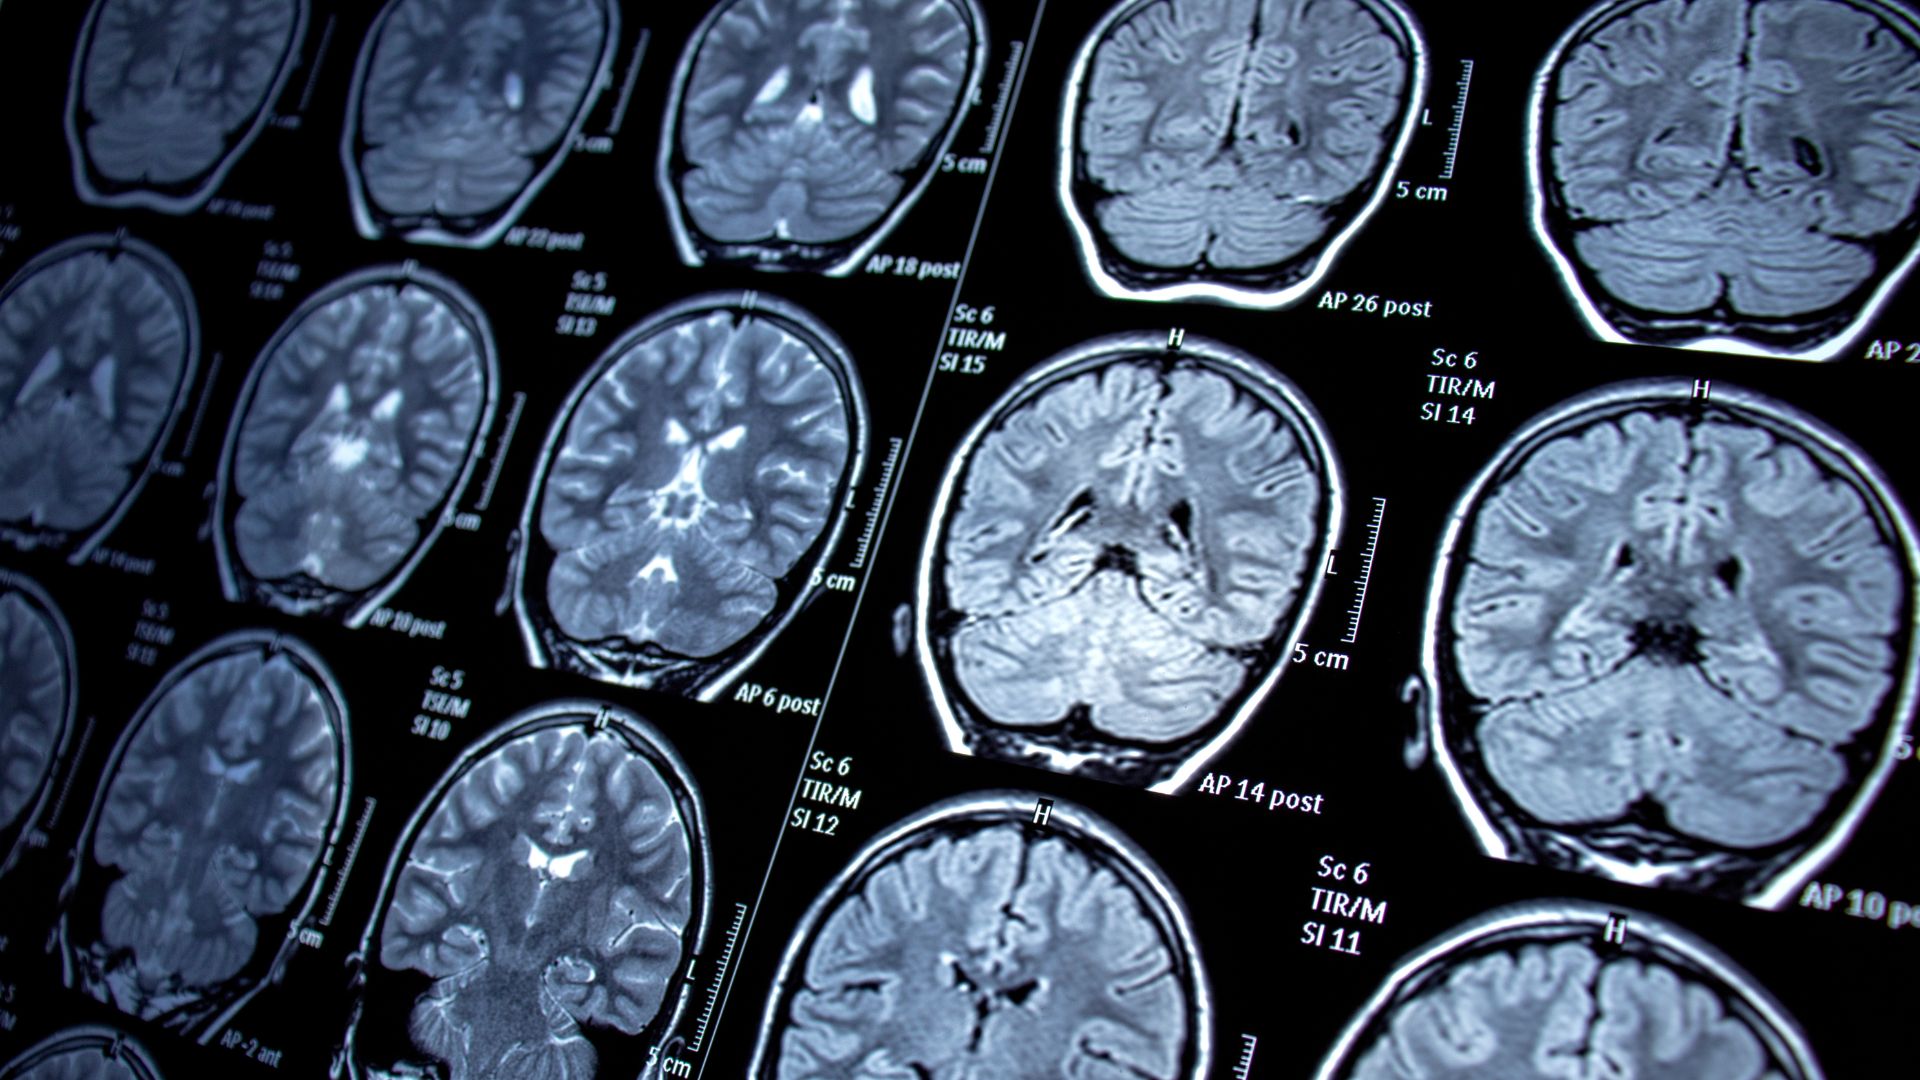

MRI scans have transformed medical diagnostics by providing detailed images of the body’s internal structures. As one of London’s few dedicated MRI clinics, we regularly see patients requiring specialised scans of specific areas, with the lower back, knees, and brain being the most common.

MRI scans utilise magnetic fields to generate precise images of the body’s internal organs and tissues. Unlike X-rays or CT scans, an MRI scan does not use ionising radiation, making it a safer option for many patients. By capturing images across multiple planes, the scan offers a thorough view of the area being examined.

MRI produces images in multiple planes, allowing for accurate diagnosis across a range of conditions.

- Brain: to check for tumours, ischaemia, or other anomalies.